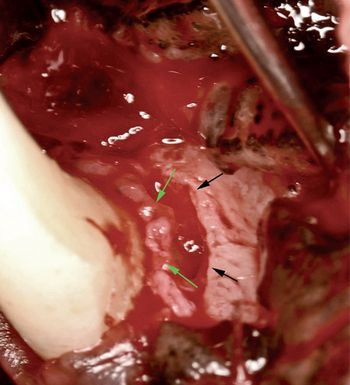

Decision making and techniques to simplify dental extractions in cats have been previous described.1-5 Proper perioperative planning and decision making regarding feline extractions can improve surgical outcome.

Decision making and techniques to simplify dental extractions in dogs have been described. Proper perioperative planning and decision making regarding canine extractions can improve surgical outcome.